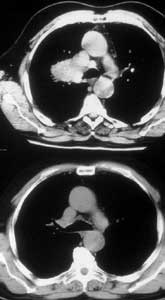

Infiltration of the PA on the right side requiring arterial reconstruction is less frequent. Partial resection of the PA often is performed in conjunction with right upper lobe sleeve resection (Figure 13). After right upper sleeve lobectomy en bloc with partial resection of the PA, the stump of the main bronchus and the PA defect are left open in the field (Figure 14). Harvesting of the pericardium is performed as above, based on the size of the portion of the resected pulmonary artery. Patch reconstruction of the PA is completed as above before reimplantation of the bronchus to reduce the arterial clamping time (Figure 15).